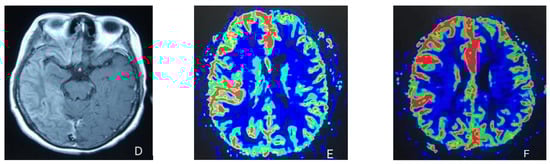

At the age of 51, she had a migraine attack with weakness in the left limb. The headache became increasingly serious, so she was admitted to a hospital six days after the attack. Upon admission, she had severe headaches and left limb weakness, and the neurological examination revealed left hemiparalysis with muscle strength at 3/5 by manual muscles testing (MMT). A brain MRI (magnetic resonance imaging) on day two of admission revealed cortical swelling in the right cerebral hemisphere (Figure 1A), and on the day three of admission, the magnetic resonance angiography (MRA) showed a slight decrease in the branches of the left middle cerebral artery (MCA). The main trunk of the left posterior cerebral artery (PCA) was slender contralateral, and its branches were significantly reduced contralaterally (Figure 1B). Symptoms persisted. On day five of admission, the patient had a focal epileptic seizure, which was followed by two more seizures. Subsequently, the patient’s left limb weakness gradually worsened, the neurologic examination revealed left hemiparalysis with muscle strength at 0/5 by MMT, and she gradually developed unconsciousness to light coma. Brain CT scans during coma revealed swelling of the right cerebral cortex (Figure 1C). Contrast-enhanced brain MRI showed swelling and diffuse enhancements in the cortex of the right cerebral hemisphere (Figure 1D). Perfusion-weighted imaging (PWI) showed right hemisphere hyperfusion (Figure 1E). Based on her medical history and presentation at admission, a lumbar puncture was performed, and the cerebrospinal fluid pressure (CSF) was 204 mm H2O. The biochemical and cytologic examination of the CSF revealed normal chloride, glucose and cell counts and classifications, in addition to normal protein levels. The CSF tested negative for bacteria, viruses, fungi and autoimmune encephalitis. Whole-exome sequencing showed a missense mutation (c.2473G > A, p.Glu825Lys) in exon 18 of ATP1A2. Based on a series of tests, the patient was diagnosed with FHM2 caused by a pathogenic ATP1A2 mutation. During hospitalization, we dehydrated the patient, gave the patient paracetamol for symptomatic treatment and an intramuscular injection of phenobarbital to control seizures. On the 15th day after admission, consciousness and hemiplegia improved, and the headache was relieved; the patient was discharged after 22 days. She was back to normal, and at later follow-up, the patient’s brain MRI (Figure 2A), contrast-enhanced brain MRI (Figure 2B), PWI (Figure 2C) and computed tomography angiography (CTA) all returned to normal (Figure 2D). The time course diagram of the disease in our patient is presented in Figure 3.

Figure 3.

Time course of the disease. Diagram illustrating time course of disease in our patient.